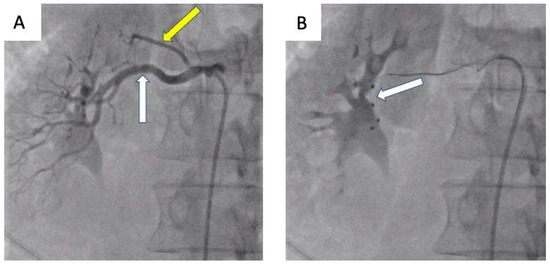

- Możeńska, O.; Rosiak, M.; Gziut, A.; Gil, R.J.; Kosior, D.A. First-in-man experience with renal denervation of multiple renal arteries in a patient with solitary kidney and resistant hypertension. Pol. Arch. Intern. Med. 2017, 127, 60–62. [Google Scholar] [CrossRef]

- Tokarek, T.; Rajtar-Salwa, R.; Rzeszutko, Ł.; Bartuś, S. Long-term benefit of redo sympathetic renal denervation in a patient with resistant hypertension. Postep. Kardiol. Inter. 2021, 17, 239–241. [Google Scholar] [CrossRef] [PubMed]

- Atas, H.; Durmus, E.; Sunbul, M.; Mutlu, B. Successful accessory renal artery denervation in a patient with resistant hypertension. Heart Views 2014, 15, 19–21. [Google Scholar] [PubMed]